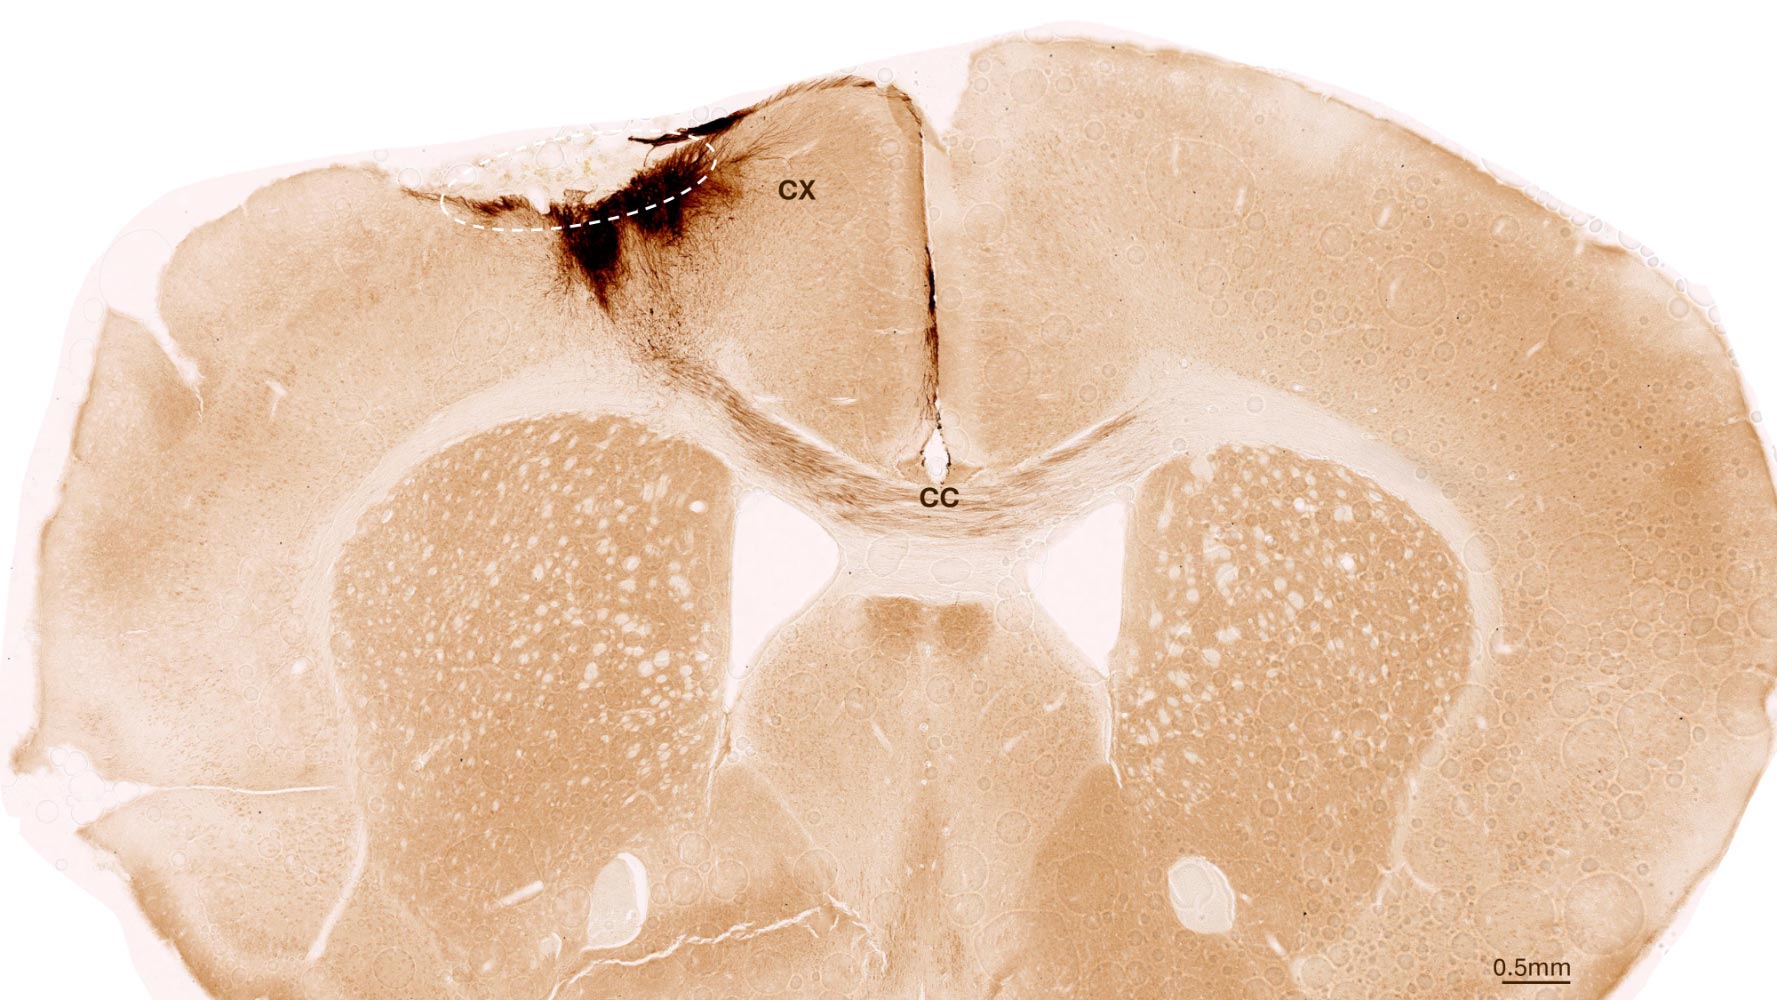

Stroke Damage Reversed As Stem Cells Regrow the Brain SciTech Daily - October 2, 2025

Stem cell therapy reversed stroke damage in mice, regenerating neurons and restoring movement.